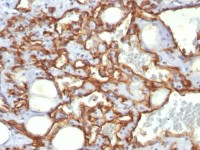

NCS1 antibody detects NCS1 protein at on mouse fore brain by immunohistochemical analysis.

Sample: Paraffin-embedded mouse fore brain.

NCS1 antibody (GTX105552) dilution: 1:500.

Antigen Retrieval: Trilogy™ (EDTA based, pH 8.0) buffer, 15min